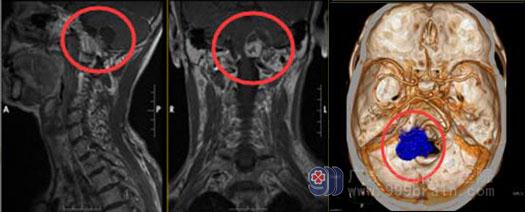

6天前,秦阿姨来到了广东三九脑科医院,头颅MR检查结果:左侧颈静脉孔区跨颅内外(颅内以左侧桥小脑角区为主)囊实性占位性病变,病灶整体范围约2.8cm×1.7cm×3.1cm,邻近脑干、左侧小脑半球受压,考虑为神经鞘瘤可能性大。医院副院长、神经外五科主任鲁明详细查阅了秦阿姨的影像资料,发现其左侧经静脉孔区跨颅内外有囊性病变,参考患者的临床表现,初步诊断是“左侧颈静脉孔区跨颅内外沟通舌下神经鞘瘤”。

颈静脉孔位置深在、范围狭小,颈静脉孔区肿瘤属少见肿瘤,发病率仅约占神经系统肿瘤的0-3%;该区域是侧颅底的关键结构,解剖关系复杂,有重要的血管和神经通过,不同患者甚至同一患者的两侧颈静脉孔在大小、位置和形状上也可有明显差别。